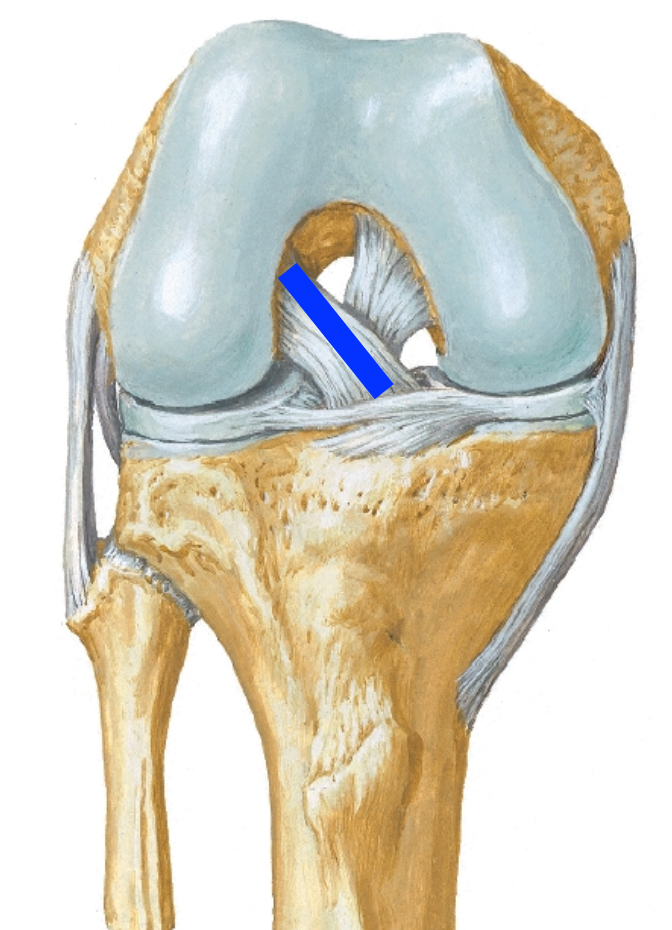

Label:

Anterior cruciate ligament origin and insertion:

APEX

Posterior cruciate ligament origin and insertion:

PAIN